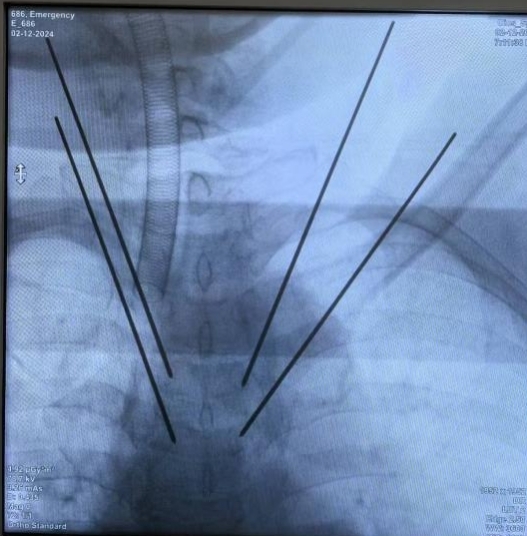

近日,我院骨病骨肿瘤外科胡勇教授团队利用手术机器人辅助,完成上胸椎转移性肿瘤的微创杂交手术。

患者,女,53岁,甲状腺癌术后2年,胸4、5及腰2椎体多发骨转移,胸背部无法药物控制的疼痛,即将病理性骨折。胡勇教授团队将MRI、3D-CT及PET-CT图像融合数据输入手术机器人进行精准规划设计,同步完成了3椎体的微创杂交手术,手术历时55分钟,术后无神经损伤并发症发生,患者疼痛消除,术后第二天即可下地行走。